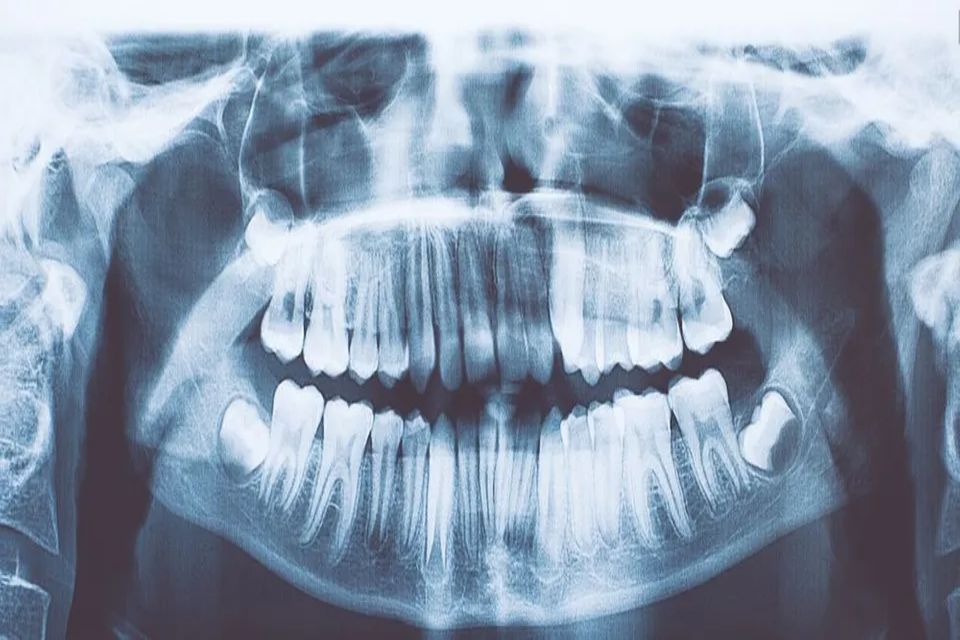

Dentsply, unico impianto al mondo garantito a vita

Lo studio Già Gilardi è specializzato nell' Implantologia a Como. Viene utilizzato Dentsply, l'unico sistema sicuro e garantito a vita per avere sempre il sorriso sulle labbra!